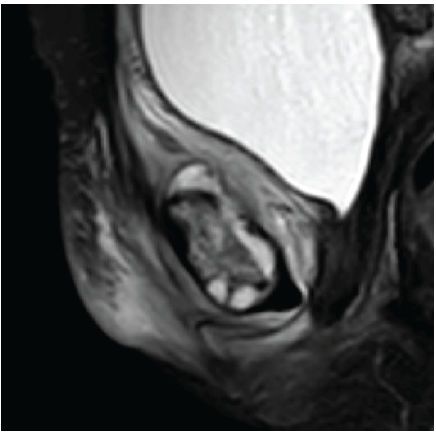

A 42-year-old South Asian woman with a history of hypothyroidism and recurrent UTIs presented with a 2-week history of lower abdominal pain radiating to both lower limbs, associated with high-grade intermittent fever. The pain was spontaneous in onset, progressive, and unrelated to trauma. She had previously received multiple short courses of antibiotics for recurrent UTIs. She presented to our center 10 days after the onset of symptoms. On evaluation, she was febrile (temperature 102°F), with suprapubic tenderness and restriction of active and passive hip movements bilaterally. Initial laboratory investigations revealed neutrophilic leukocytosis (total leukocyte count: 15,000/µL; neutrophils: 13,600/µL) and elevated C-reactive protein (195 mg/L). Urine routine examination demonstrated numerous red blood cells but no pyuria. A contrast-enhanced computed tomography renal stone survey showed perinephric stranding in the retropubic space suggestive of cystitis, with no evidence of collections, hematoma, or pelvic bone fractures. She was empirically started on intravenous piperacillin-tazobactam for presumed acute cystitis, given her history of recurrent UTIs. However, urine culture showed no growth after 48 h, while blood cultures grew MRSA. Antibiotics were escalated to intravenous teicoplanin (400 mg twice daily). Despite 48 h of appropriate therapy, she continued to have high-grade fever and worsening excruciating suprapubic pain radiating to the groin and medial thighs, severely limiting her mobility. Magnetic resonance imaging (MRI) of the pelvis with contrast revealed osteomyelitis of the bilateral pubic bones and superior pubic rami, with abscesses (10 mL and 1.5 mL) around the pubic symphysis, fluid collections in the right adductor and obturator externus muscles, and edema of the obturator internus, externus, and pectineus muscles (Figs. 1, 2, 3, 4).

Figure 2: Sagittal magnetic resonance imaging image demonstrating a well-defined collection in the superior aspect of the pubic symphysis (approximately 10 cc), suggestive of an abscess. The collection shows peripheral enhancement without extension into the abdominal cavity.

Figure 3: Sagittal magnetic resonance imaging showing a smaller abscess (~1.5 cc) in the inferior aspect of the pubic symphysis. Associated edematous changes are noted in the adductor muscle compartment, obturator externus, and pectineus muscles.